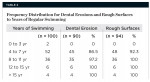

Similar findings related to the number of years of regular swimming and the prevalence of erosion and rough surfaces were noted (Table 2). Those who had been swimming for 0 to 3 years, 4 to 7 years, 8 to 11 years, 12 to 15 years, and more than 15 years showed (0% DE, 0% RS), (86.5% DE, 92.3% RS), (97.2% DE, 100% RS), (100% DE, 100% RS) and (100% DE, 100% RS), respectively.